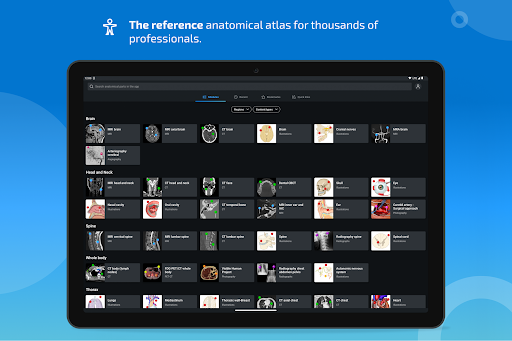

جديد: يمكنك الآن تصفية الوحدات حسب المنطقة أو نوع المحتوى حتى تتمكن من العثور على الوحدة التي تبحث عنها بشكل أسرع.